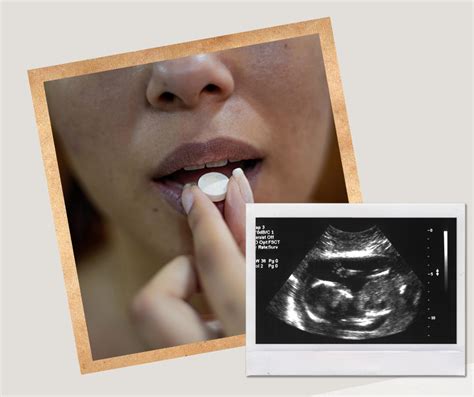

E. Kuliešytė pateikia naują pažangesnį nėštumo nutraukimo metodą taikančią Suomiją, kurioje leidžiamas medikamentinis nėštumo nutraukimas. Lietuvoje jis neįteisintas. „Kai buvau Suomijoje, didžiojoje Helsinkio klinikoje, neradau jos ataskaitose informacijos apie abortus. Man buvo paaiškinta, kad nėštumo nepageidaujančios moterys nutraukia nėštumą medikamentais ambulatoriškai. Iki 6-7 nėštumo savaičių galima naudoti tam skirtas tabletes. Metodas yra aprašytas PSO. Moterys renkasi medikamentinį abortą, nes jis teikia privatumą, neatliekama chirurginė intervencija, todėl yra mažesnė rizika infekcijai, kitoms komplikacijoms. Medikamentinis nėštumo nutraukimas, jei atliekamas tinkamai, panašus į savaiminį persileidimą, nereikia gulėti ligoninėje, nenukenčia darbingumas.“ R. Nadišauskienė atkreipė dėmesį, kad ir Estijoje jau senokai yra įteisinti medikamentiniai abortai.

Vaistinio nėštumo nutraukimą kitur pasaulyje paprastai renkasi dauguma moterų - taip yra Jungtinėje Karalystėje, Estijoje, Suomijoje, Švedijoje. Lietuvoje statistika nėra renkama, tačiau Valstybinės vaistų kontrolės tarnybos (VVKT) duomenys rodo, kad per mėnesį yra nuperkama 10-30 tablečių rinkinių. Tačiau susidomėjimas naujove atsirado ir net didėja. Tai rodo tie patys vaistų pardavimo duomenys.

Daug gydytojų moteris nuo aborto - tiek medikamentinio, tiek chirurginio - bando atkalbėti. Seime pernai net buvo iškelta Iniciatyva, kad tokios konsultacijos prieš abortą būtų privalomos ir apmokamos iš valstybės biudžeto, jos pavadintos „krizinio nėštumo“. BENDRA.lt kalbintos moterys tvirtina, kad būtent atkalbinėjimas ir buvo nemaloniausia aborto procedūros dalis, nes jos buvo tvirtai apsisprendusios. Pavyzdžiui, Indrė (vardas pakeistas - BENDRA.lt), nuėjusi pas gydytoją dėl aborto, gavo embriono ultragarso nuotrauką ir sulaukė replikos, esą tai galėtų būti pirmoji nuotrauka jos šeimos albume. Taip pat gydytoja ją...